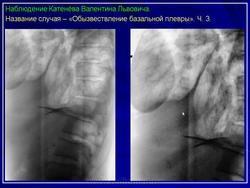

Плевральная кальцификация.

Продолжение.